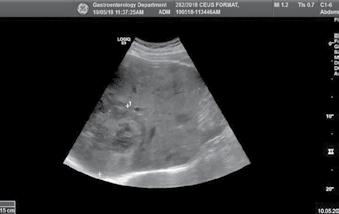

Angiosarcomul hepatic – prezentare de caz

As. Univ. Dr. Ana Maria Ghiuchici, Conf. Univ. Dr. Mirela Danilă, Conf. Univ. Dr. Maria Cornianu, Dr. Nicoleta